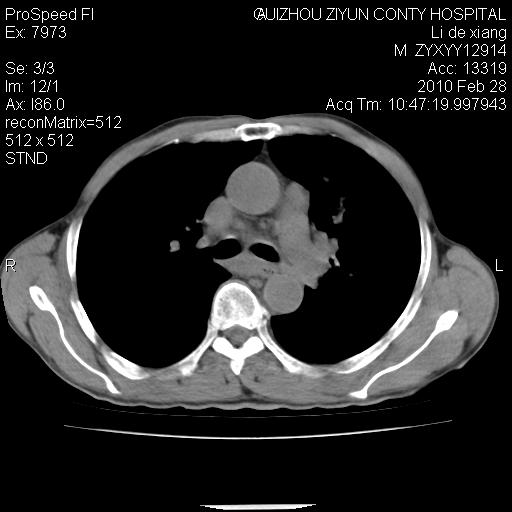

标题: CT24776:男 71Y 咳嗽咳痰胸痛两月,伴声音嘶哑。 [打印本页]

标题: CT24776:男 71Y 咳嗽咳痰胸痛两月,伴声音嘶哑。

左侧中央型肺癌伴左肺上叶阻塞性肺炎及节段性不张可能性大,建议纤支镜检查!

左侧中央型肺癌伴左肺上叶阻塞性肺炎及节段性不张可能性大,建议纤支镜检查!纵隔淋巴结转移.

左侧中央型肺癌伴左肺上叶阻塞性肺炎及纵隔淋巴结转移。

左肺门部肿块,伴左上肺斑块影,周边模糊,支持左肺中央型肺癌伴节段性不张及阻塞性肺炎,结合支气管镜检查。

患者有声音嘶哑,若时间长了,没改变,喉镜检查无异常,可考虑左侧喉返神经受累,因为:左侧喉返神经绕主动脉弓或肺动脉韧带的主动脉端,沿气管与食管之间的沟上行至颈部.

支持肺癌.

左上叶支气管狭窄,阻塞性病变,肺门肿块,纵隔及肺门淋巴结增大,中央性肺癌

左肺中央型肺癌并阻塞性改变、纵膈 淋巴结转移